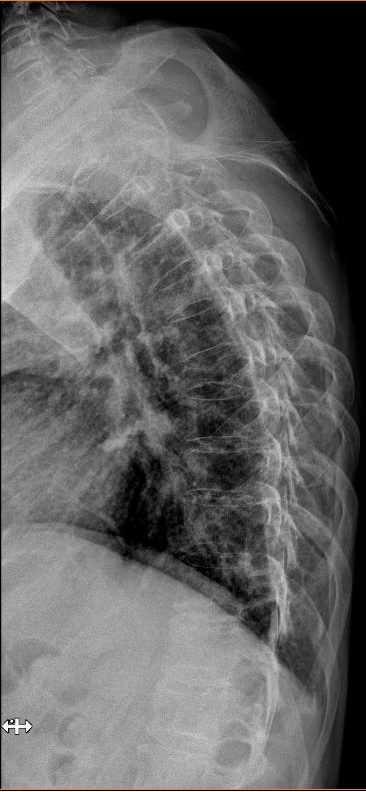

En la exploración física destaca un dolor al realizar la bidepstación y dolor a la palpación de apófisis espinosas dorsales D6 hasta L1 e imposibilidad a la movilización a la flexión, extensión y rotación de columna, resto sin alteraciones.

Se realiza radiografía de lumbar, dorsal y destaca chafamiento de D4 y una disminución radiodensidad ósea en todos los cuerpos vertebrales.

A su llegada a urgencias se realiza analítica complementa y una tomografía computerizada dorsolumbar objetivandose metástasis óseas cervical, dorsal D4, D6, D12 y afectación cuarto arco costal, se decide ingreso para estudio diagnosticándose un mieloma múltiple.